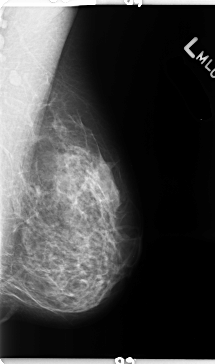

B_3132_1.LEFT_MLO

LEFT_MLO LINES 4728 PIXELS_PER_LINE 2792 BITS_PER_PIXEL 12 RESOLUTION 50 NON_OVERLAY